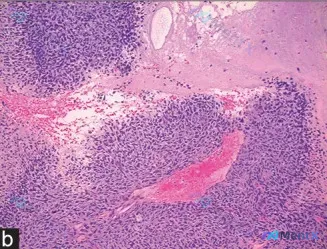

这张皮肤病理HE片:梭形细胞+多核巨细胞,你第一反应会怎么归类?

整理了一张皮肤/黏膜的HE染色病理镜下图像资料,大家一起来看看第一反应会怎么考虑。 先把能看到的关键信息列出来: 1. 左上角明确可见复层鳞状上皮(皮肤表皮) 2. 下方真皮层正常结构被破坏,被病变替代 3. 病变细胞:大量梭形细胞,呈束状/漩涡状排列,混杂散在多核巨细胞 4. 核的表现:显著多形性...